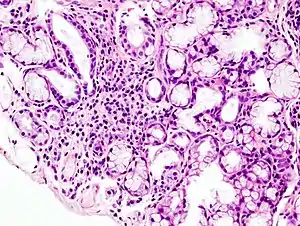

Image with a microscope of focal lymphoid infiltration in the minor salivary gland associated with Sjögren syndrome.

While the exact cause is unclear, it is believed to involve a combination of genetics and an environmental trigger such as exposure to a virus or bacterium.[4] It can occur independently of other health problems (primary Sjögren's syndrome) or as a result of another connective tissue disorder (secondary Sjögren's syndrome).[3] Sjögren's syndrome may be associated with other autoimmune diseases, including rheumatoid arthritis (RA), systemic lupus erythematosus (SLE) or systemic sclerosis. The inflammation that results progressively damages the glands.[7] Diagnosis is by biopsy of moisture-producing glands and blood tests for specific antibodies.[2] On biopsy there are typically lymphocytes within the glands.[2]

A lip/salivary gland biopsy takes a tissue sample that can reveal lymphocytes clustered around salivary glands, and damage to these glands from inflammation. This test involves removing a sample of tissue from a person's inner lip/salivary gland and examining it under a microscope. In addition, a sialogram, a special X-ray test, is performed to see if any blockage is present in the salivary gland ducts (i.e. parotid duct) and the amount of saliva that flows into the mouth.[44]

A radiological procedure is available as a reliable and accurate test for Sjögren's syndrome. A contrast agent is injected into the parotid duct, which opens from the cheek into the vestibule of the mouth opposite the neck of the upper second molar tooth. Histopathology studies should show focal lymphocytic sialadenitis. Objective evidence of salivary gland involvement is tested through ultrasound examinations, the level of unstimulated whole salivary flow, a parotid sialography or salivary scintigraphy, and autoantibodies against Ro (SSA) and/or La (SSB) antigens.